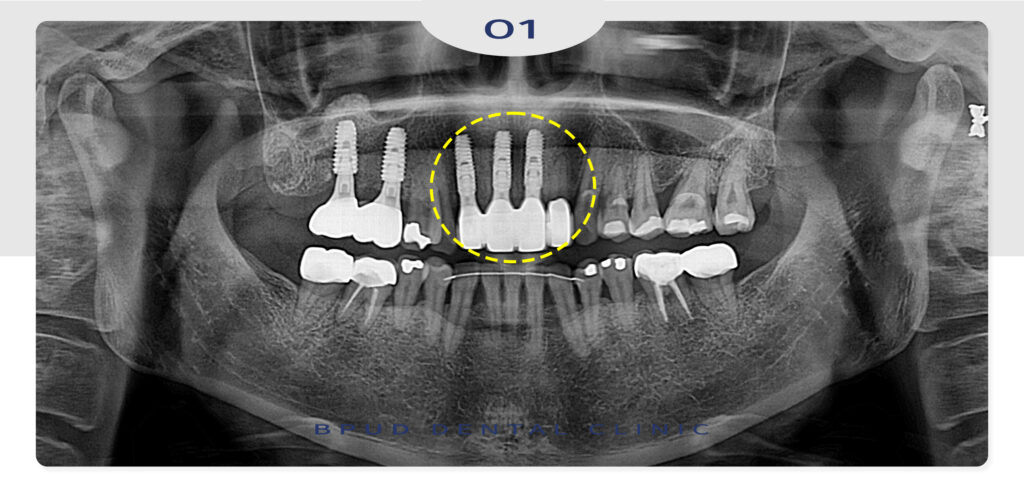

25.09.06

25.09.29

환자분께서는 어려워 걱정이 많았던

상악동 거상술도 쉽게 해결해서 만족해하셨고

앞니 부분도 누공 때문에 신경이 많이 쓰였는데

잘 해결되고 심미성까지 회복되어 매우 만족스럽다는

말씀을 전해주셨습니다.

25.07.10

앞니 임플란트도 섬세한 시술이 필요한데요.

앞니는 어금니보다 잇몸뼈가 얇고

뼈흡수가 빠르게 진행되는 부위이기 때문에

치아를 잃은 뒤 치료를 미루면 그만큼 뼈가 줄어들어

뼈이식이 필요해지고 이는 곧 치료 기간의 연장과

비용 상승으로 이어집니다.